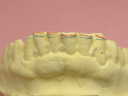

補綴物物 完成

模型上では、1.1下部孤形空隙が広いように

見えますが、歯肉模型にて調整して

歯肉を圧迫せず、息が漏れることが無いように

調整しました |